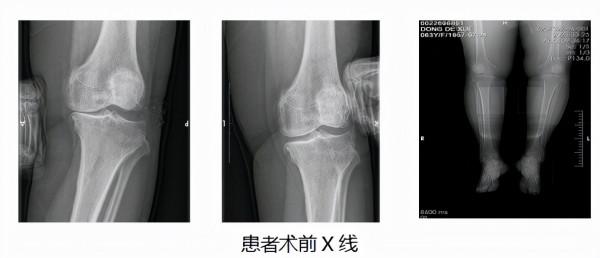

宋科官教授檢查後發現,患者膝關節症狀侷限於內側,內側存在明顯壓痛,而且被動活動度尚可。經X線檢查發現,內側間隙在側方應力作用下明顯變窄,外側間隙尚可,提示前內側骨性關節炎。針對董阿姨的病情與年齡,宋科官教授、劉寧副教授選擇相對於全膝表面置換術切口更小、創傷更小、恢復更快的微創手術方式——單髁置換術,來解決董阿姨的病痛。